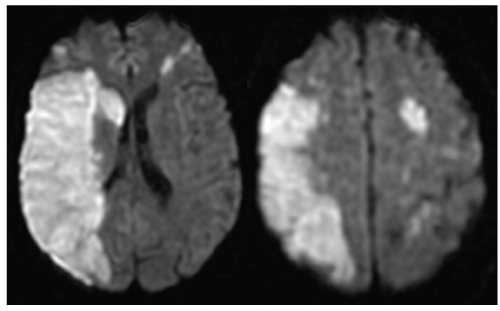

Figure 1: Brain MRI

Axial diffusion-weighted imaging (DWI) MR images showing a large hyperintense lesion in the right middle cerebral artery territory (A) and fronto-parietal hyperintense lesions in the left hemisphere consistent with infarctions (B)